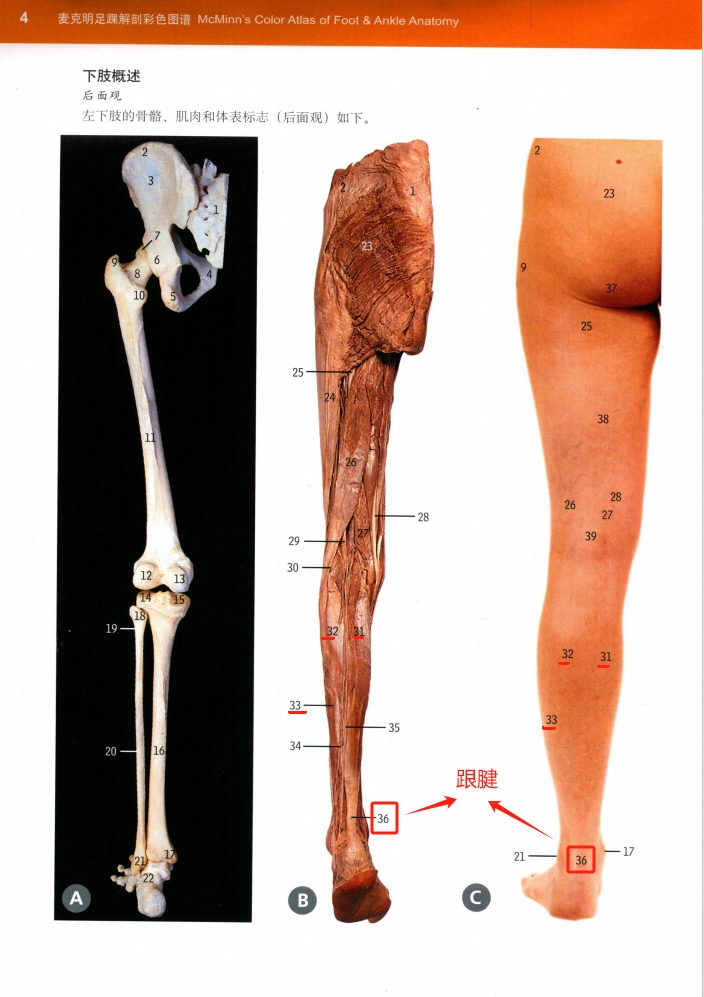

图说:腓肠肌(31,32)与比目鱼肌(33)的腱性部分汇合构成跟腱(36),即通常所说的 Achilles 腱 资料来源©《麦克明足踝解剖彩色图谱(第四版)》第4页

- 麦克明足踝解剖彩色图谱(第四版) 人民军医出版社 张建中 译